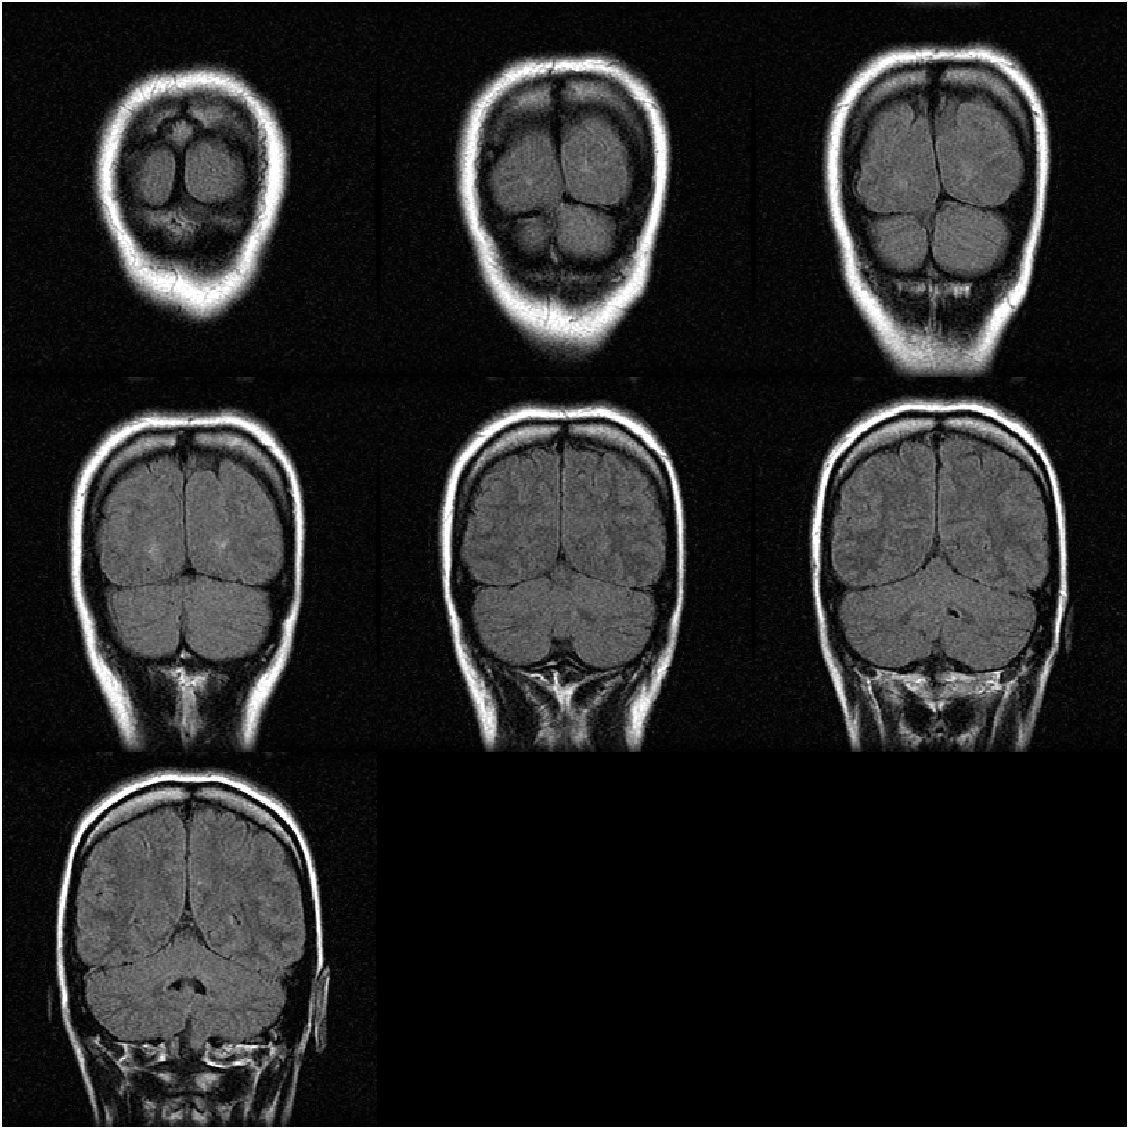

Example 1: create montage from multi-frame image (3-D array)

montage function can directly accept the image array as input. Take gray images, which have only one single color channel, as an example:

where code load mristack is used to load an MRI (Magnetic Resonance Imaging) data set, which only includes a 3-D uint8-class array mristack storing the pixel data of 21 gray images:

mristack 256x256x21 1376256 uint8

We can specify the number of images to be displayed by setting "Indices" property, like showing the first seven images for example:

img = montage(mristack,"Indices",1:7);